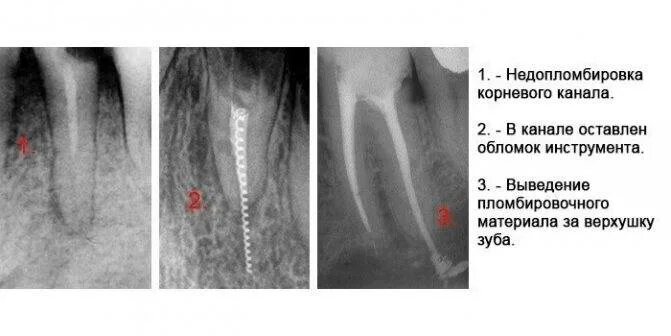

Воспаление зуба после удаления нерва